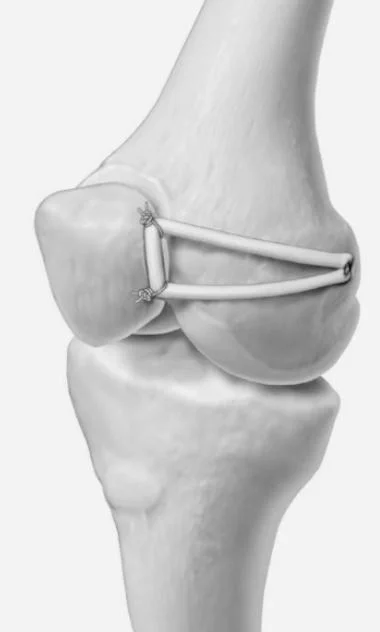

• Medial Patellofemoral Ligament Reconstruction

Medial Patellofemoral Ligament Reconstruction